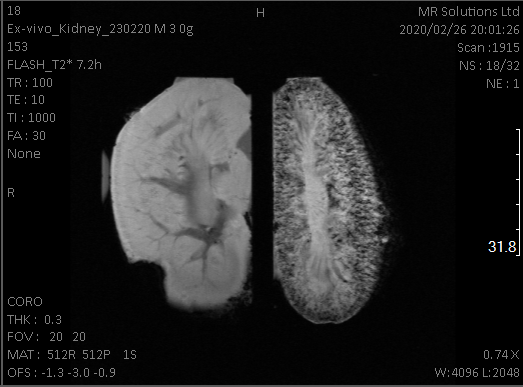

mri_kidneys

Kidneys - without & with ferritin